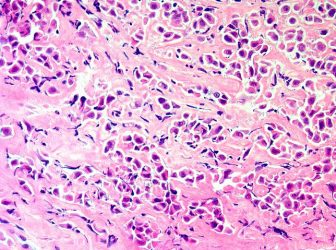

Malignant pleural mesothelioma is an aggressive malignancy of the pleural surface, predominantly caused by prior asbestos exposure. It only takes a few months for untreated mesothelioma symptoms to worsen and become severe. Learn more about symptoms, diagnosis, and treatments available for pleural mesothelioma is a dangerous cancer that affects the lining of the lungs (the pleura). Average life expectancy is around one year with treatment.